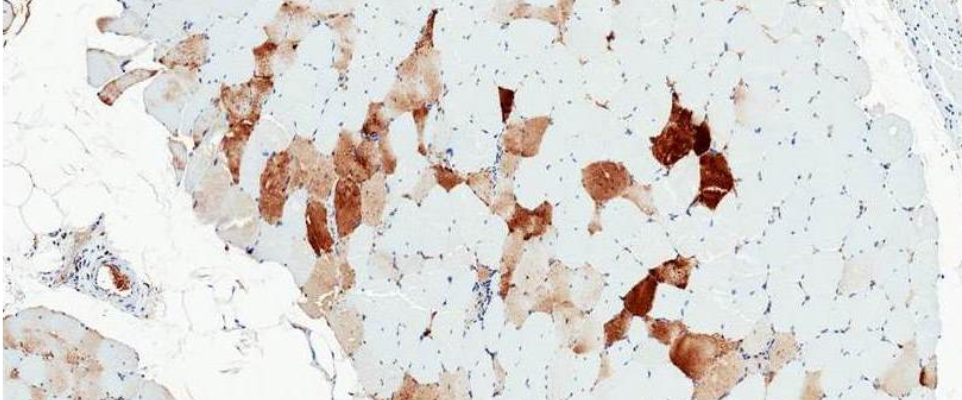

This image shows muscle tissue where individual muscle fibers can be identified. This muscle biopsy comes from a patient who received intramuscular injections of a gene therapy vector expressing AAT as part of our clinical trial. The brown color indicates presence of AAT protein. As AAT is not normally expressed in muscle, the presence of the protein is vector-related.

This strategy has already been tested in clinic trials. We showed that the transduced muscle fibers do express AAT, which is normally not present in muscle tissue (see image on top of this page). Unfortunately, in our first trial the serum AAT levels that were achieved in the patients were too low to be therapeutic. However, we have since then generated a second generation vector that is much more potent in preclinical studies, and we are hoping to move this forward in the near future.